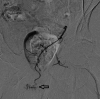

Prostate artery embolization (PAE) is a technically challenging angiographic therapy that has been shown to have excellent clinical outcomes for men with benign prostatic hyperplasia and lower urinary tract symptoms. Although clinical outcomes have been well documented, several questions remain regarding various technical details of the procedure. This article is a brief review of indications and technical parameters of PAE as well as commonly debated topics throughout the literature. Finally, the article serves to report tips and tricks from a high-volume center.